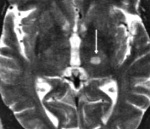

I63.9 Инфаркт мозга неуточненный